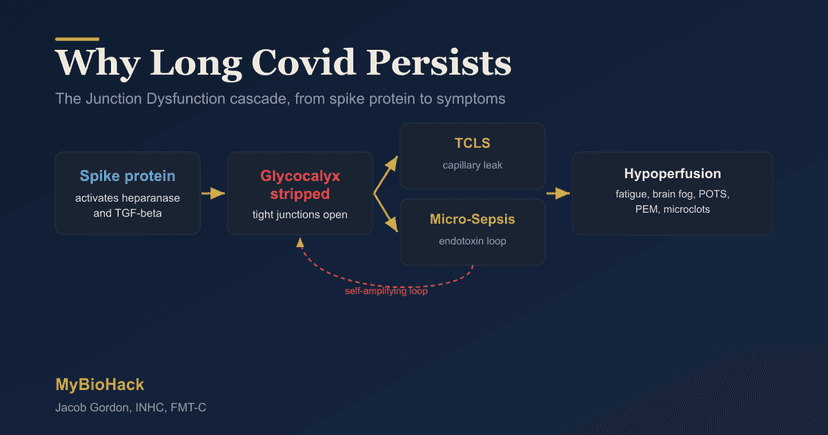

Vascular Health

7 Steps to Naturally Treat Long Covid (Science-Based Protocol)

11 min read